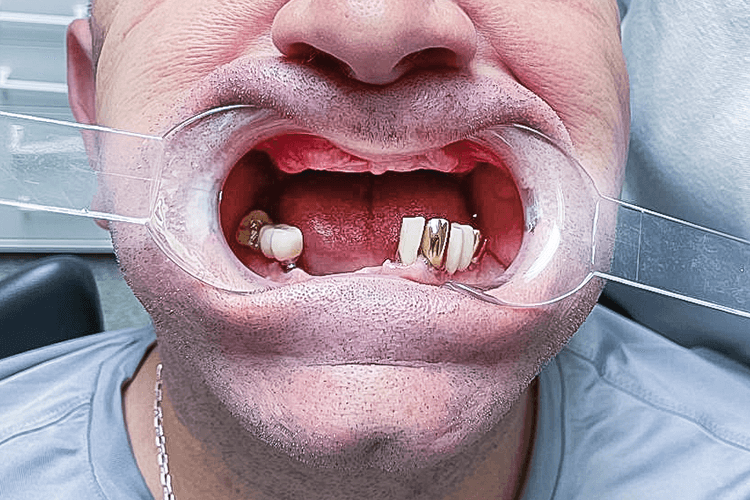

До нас звернувся пацієнт 1971 року народження зі скаргами на повну адентію верхньої щелепи та множинну адентію нижньої щелепи (від п’ятого зуба справа до другого зуба зліва), а також на рухомість мостовидного протезу нижньої щелепи, який покривав зуби 3, 4, 5 та 6 з лівого боку. Головна проблема для пацієнта — неможливість пережовування їжі та естетичний дефект.

Під час огляду та діагностики нижньої щелепи було виявлено захворювання тканин пародонту в області опорних зубів мостоподібного протезу, 2 імплантати виробництва Південної Кореї з правого боку в області зубів 5 та 6, а також, ретинований "зуб мудрості" з правого боку. Додатково, пацієнт повідомив що не може використовувати знімні протези через посилений блювотний рефлекс та загальний дискомфорт в експлуатації подібних конструкцій.